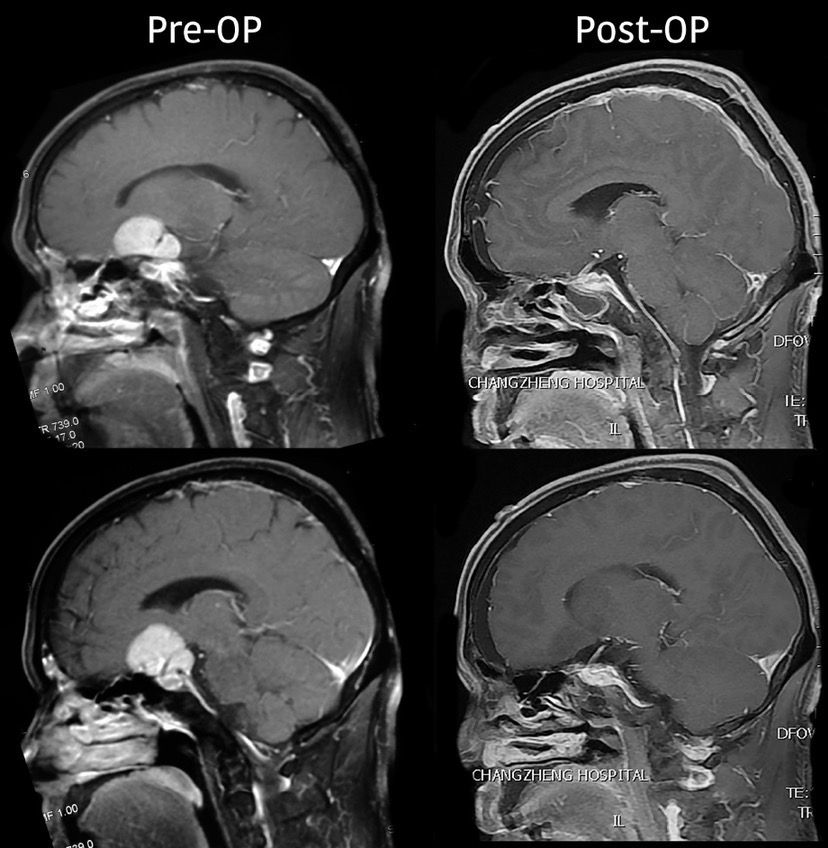

MRI检查:

术后MRI复查: